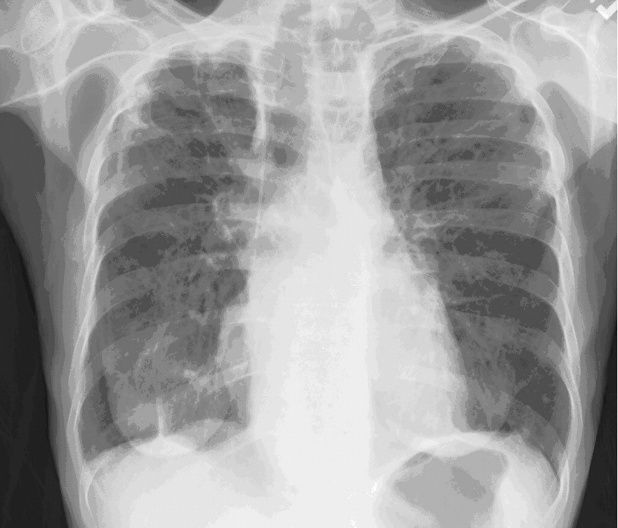

再次行支气管镜检查,并于颈部完全屈曲位将气管插管尖端精准定位于气管隆嵴正上方。胸部X线及CT影像显示纵隔增宽伴食管重度扩张,双侧主支气管受压(图2、图3)。

图2. 胸部X线. 胸部CT示食管重度扩张,导致喉部(A)、气管(B)及双侧主支气管(尤其右侧)(C)前向移位伴压迫[2]